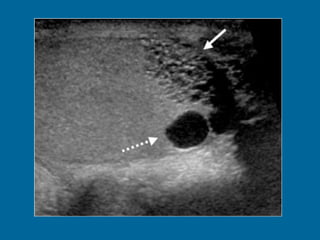

Transverse US scan of the testis shows a normal transmediastinal artery (arrow) as a linear hypoechoic band. Color Doppler flow US (not shown) revealed flow through the vessel.

Transverse US scanof the testis shows a normal transmediastinal artery (arrow) as a linear hypoechoic band. Color Doppler flow US (not shown) revealed flow through the vessel.